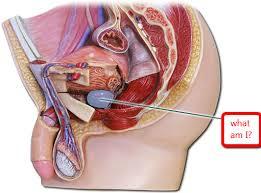

Broad ligament

Cervix

Clitoris

Endometrium

Labia majora/minora

Myometrium

Perimetrium

Uterine (=fallopian) tube

Uterus

Vagina

Vaginal orifice

Vestibule (of vulva)